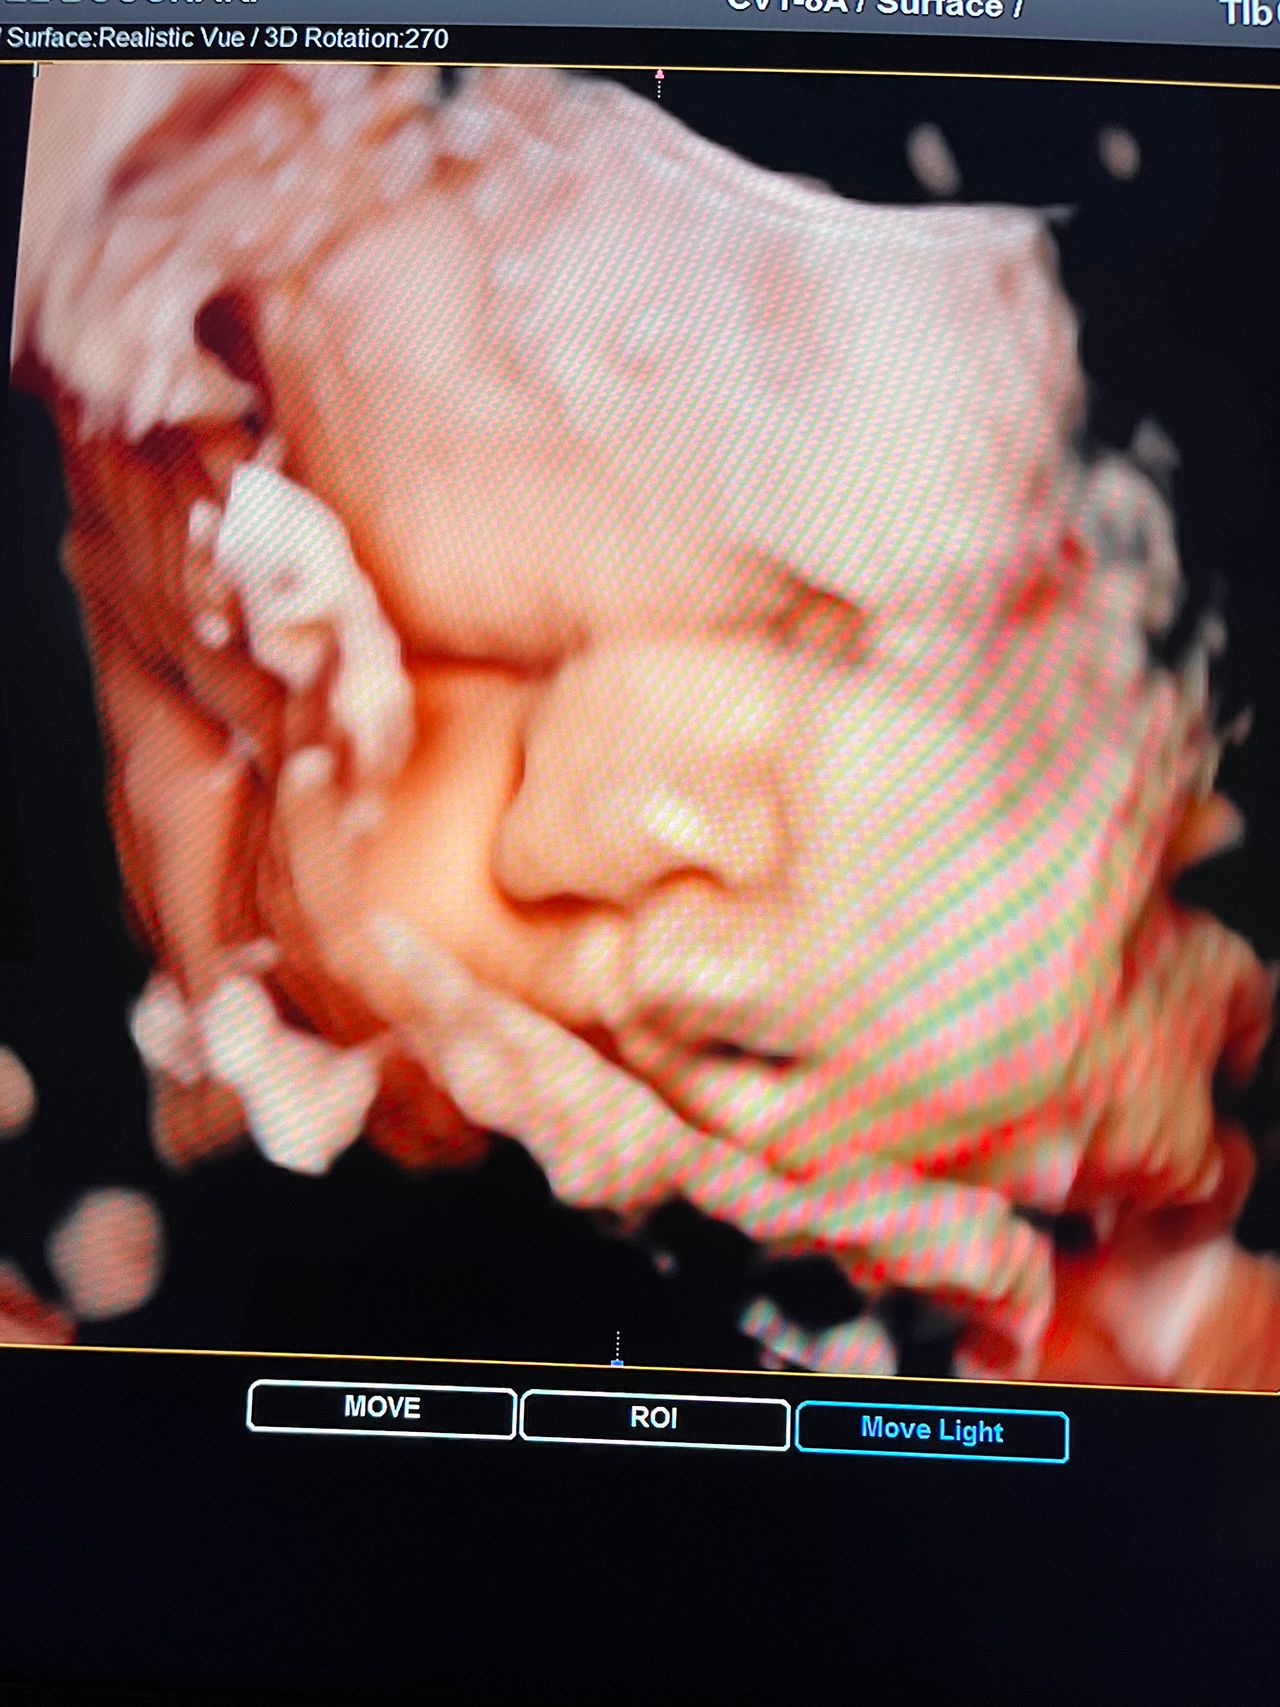

Attualmente lavoro come Dirigente medico nella SC di Ostetricia e Ginecologia dell'Ospedale Michele e Pietro Ferrero di Verduno, mi occupo prevalentemente di screening prenatale, ecografia ostetrica del I trimestre( misurazione translucenza nucale,NT), ecografia morfologica del II trimestre, ambulatorio pregresso taglio cesareo, ecografia ostetrica 3D. Seguo le gravidanze fisiologiche e quelle ad alto rischio , presto servizio in sala parto. Eseguo visite ginecologiche di I-II livello in regime ambulatoriale, counseling contraccettivo ed eventuale prescrizione pillola, inserimento spirale (IUD), dispositivo sottocutaneo (Nexplanon).

Foto e video